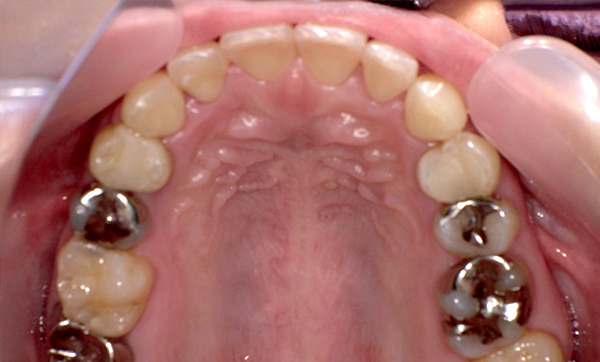

症例_009 「上下の前歯」症例

治療期間:7ヶ月金額:54万円+税20代女性捻転歯一部の反対咬合前歯のガタガタ